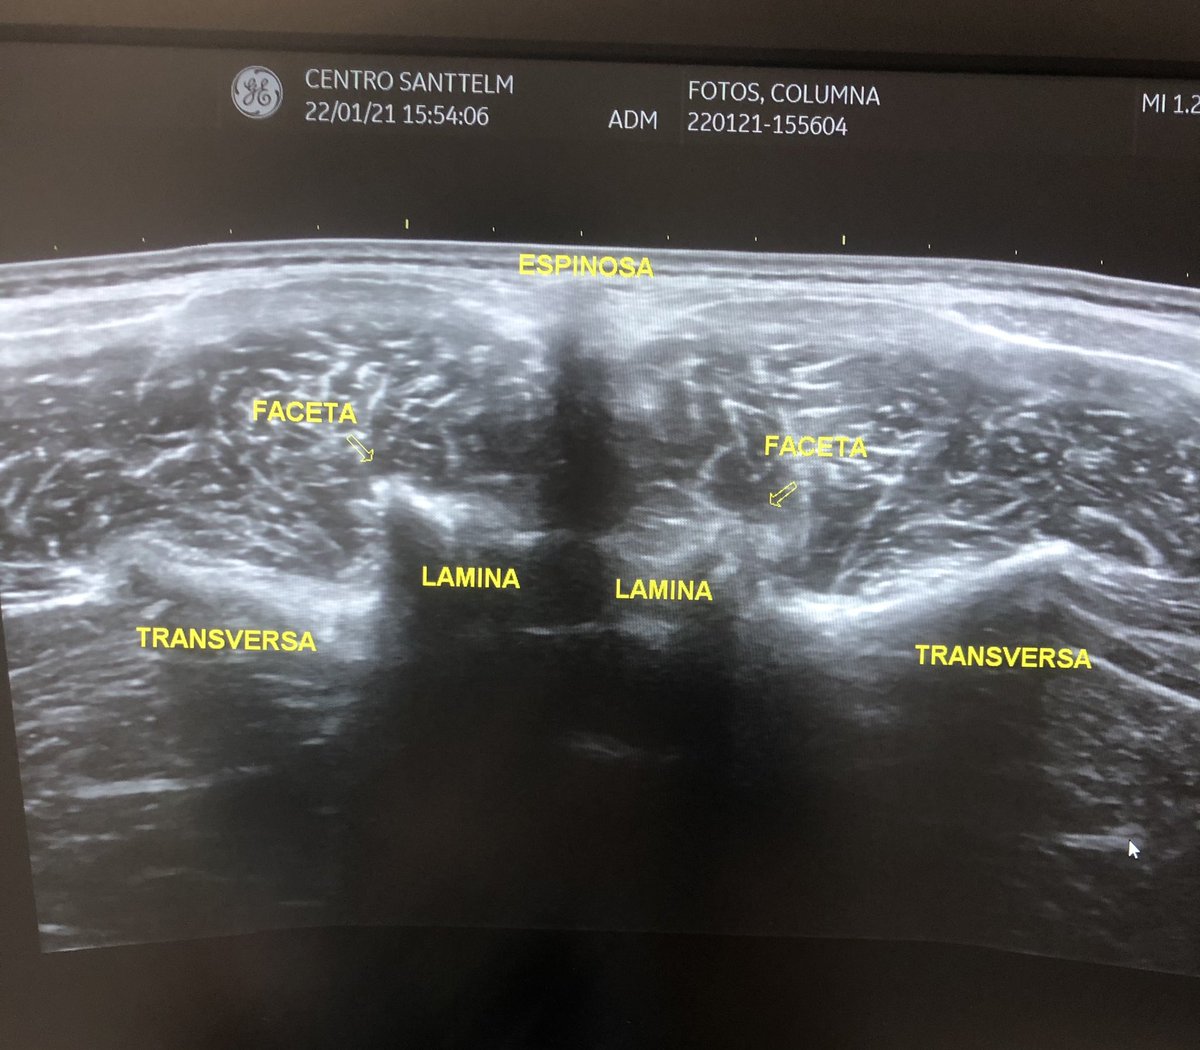

Ecografía vertebral lumbar #centrosanttelm #ecografia #sonography #neuroeje #fisioterapia #columnavertebral #lumbares #lumbalgia #facetas

Ecografía vertebral lumbar

#centrosanttelm #ecografia #sonography #neuroeje #fisioterapia #columnavertebral #lumbares #lumbalgia #facetas